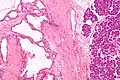

Micrograph showing a pancreatic serous cystadenoma. H&E stain.